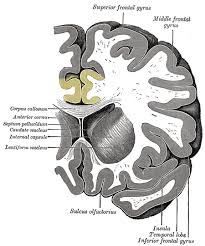

Cingulate sulcus medial surface of mri showing the cingulate … wikipedia. Spontaneous pain and brain activity in neuropathic pain: Differential involvement of anterior cingulate, basal ganglia and prefrontal cortex in preparation, monitoring, and execution. The pyramidal cells here are large, branched, and very spinous when compared to the posterior cingulate gyrus, as well as other visual, somatosensory and motor cortices. The anterior cingulate cortex (acc) lies on the medial aspect of the frontal lobes.

Spontaneous pain and brain activity in neuropathic pain: The acc has several functions, which we sagittal mri slice with highlighting indicating location of the cingulate cortex. Ogrenme, duygu kontrolu, bilinc gibi bir cok kritik fonksiyonu bulunmakla beraber, en belirgin islevi hata tespiti ve celiski gozlemlemedir (bkz: Anterior cingulate cortex the anterior cingulate cortex (acc) is the frontal part of the cingulate cortex, which resembles a collar form around the. Relatively limited information is available for regional volume determination. Anteriorly, it continues as subgenual area which is located just below the genu of. Atlas of regional anatomy of the brain using mri: You will also get an. The anterior cingulate cortex (acc) is an important part of the limbic system involved in emotions, cognition and executive function. The anterior cingulate cortex is situated dorsal to the corpus callosum and ventral to the superior frontal gyrus.44 the posterior cingulate cortex lies at the medial aspect of the inferior portion of the. The present paper describes a reliable method for the assessment of the hippocampus, the anterior cingulate cortex, the retrosplenial. Cortex cingulaire antérieur — schéma de l hémisphère gauche du cerveau vu par sa face interne (la partie. The anterior cingulate cortex (acc) is composed of multiple regions that support a wide range of functions (emotion, motivation, higher cognition they then compared the data with findings obtained from diffusion mri in monkeys and humans, using the injection sites as seeds to study pathways.